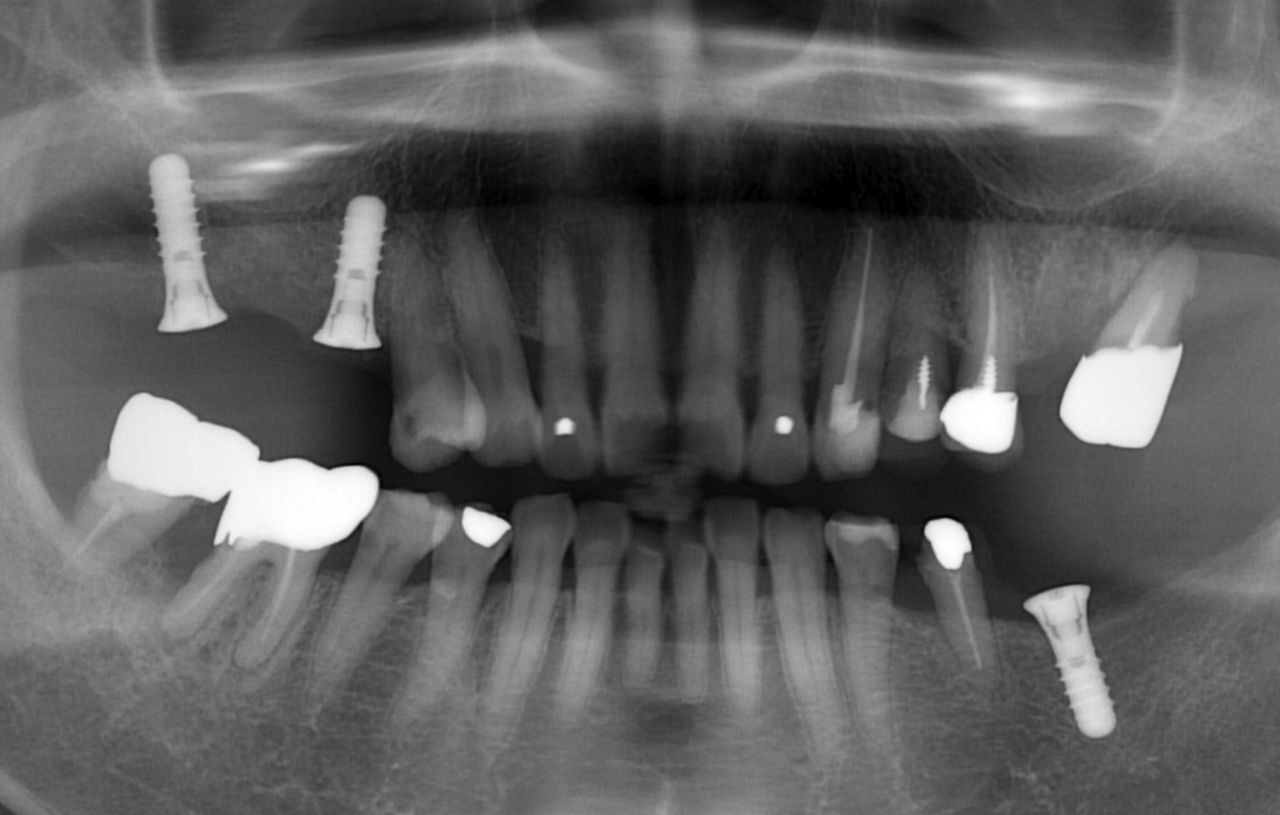

以下が初診時です。

それでは、実際の状態を見ましょう。

いつものように 骨吸収の状態を分かりやすくするために

骨吸収の状態を線で書いたのが以下のレントゲンになります。

青線が骨吸収を起こす前の骨の位置です。

赤線は、現在の骨の位置です。

さらに分かりやすくするために 骨吸収部位を赤色の領域で表します。

骨吸収が非常に進行しているのが分かるかと思います。

次に上顎洞です。

以下の緑線は上顎洞という空洞です。

緑線の内側は空洞なのです。

骨ではありません。

ただの 穴 です。

これも さらに分かりやすくするために、上顎洞 を緑色で表示します。

以下が治療後です。

現在メインテナンス(定期検査) にきちんと通われていることもあり、非常に良い状態です。